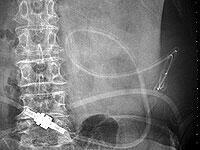

写真8は上腹部へカテーテルが移動したときに長時間排液して大網がカテーテルにはまり込み腸管の動きでカテーテルが引き伸ばされています。

注排液ができなくなったためカテーテル交換をおこないました。

一時的に排液が少ないとき、長時間排液にしたままにしたりミルキングするとカテーテルに大網などがはまりこみます。

カテーテルの側孔に大網が当たって注排液が悪くなっても吸引して側孔に引き込まない限り閉塞することはありません。